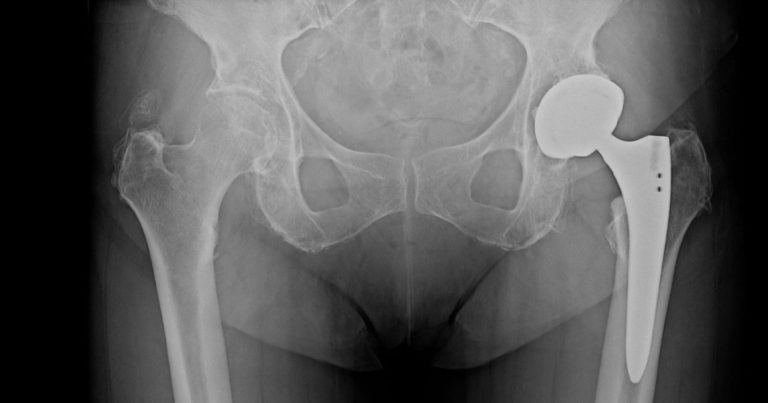

Foto Wikipedia

La coxartrosi può dipendere da molteplici fattori: sedentarietà, sovraccarico dovuto a sport o lavoro fisicamente impegnativi, predisposizione genetica, traumi pregressi, disallineamento degli arti inferiori e obesità. Una diagnosi basata su radiografia o risonanza magnetica permette di definire lo stadio della malattia e impostare il trattamento più adeguato. Nelle fasi iniziali si può intervenire con fisioterapia mirata, riposo, farmaci antidolorifici e infiltrazioni ecoguidate. In casi più delicati, invece, il chirurgo può proporre terapie biologiche con cellule staminali mesenchimali, utili per ridurre dolore e infiammazione. Quando la degenerazione è avanzata e la qualità di vita compromessa, infine, l’opzione più efficace rimane la protesi d’anca, disponibile in diverse soluzioni, comprese tecniche mini-invasive come la “bikini incision” o protesi di rivestimento pensate per pazienti giovani e sportivi.